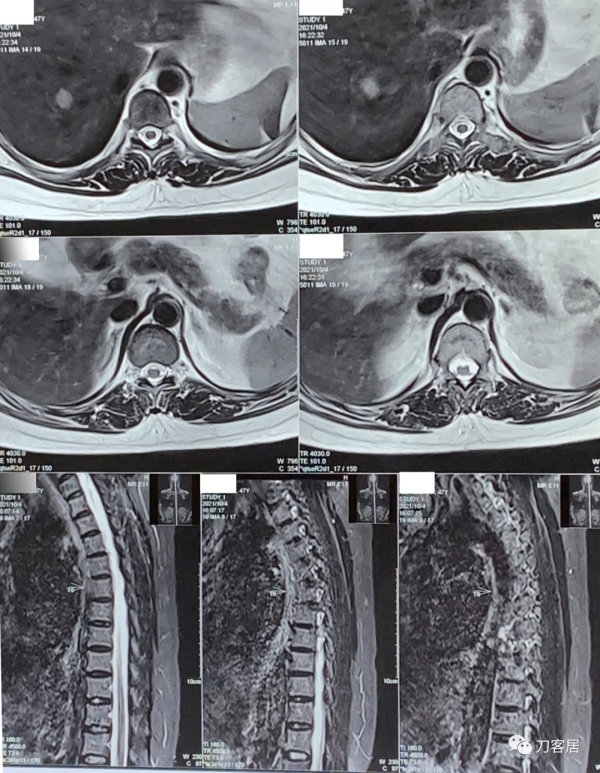

圖6. 20211004胸椎MRI矢狀面T2相,未見明確的胸椎管狹窄。

圖7. 20211004胸椎MRI矢狀面T1相,未見明確的胸椎管狹窄。

圖8. 20211004胸椎MRI矢狀面及橫截面,未見明確的椎管狹窄。